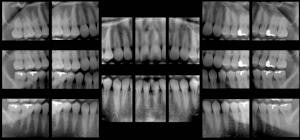

| These panoramic bitewings took 15 to 20 seconds to create, compared with 20 minutes for a full-mouth intraoral survey (Dentomaxillofacial Radiology, January 2010, Vol. 39:1, pp. 47-53). |